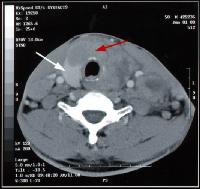

CT-scan van het abdomen of het kleine bekken

CT scan van het abdomen

Een CT-scan van het abdomen of het kleine bekken worddt genomen om eventuele problemen ter hoogte van de darmen, lever, nieren, milt, enz... te beoordelen.

Ook hier is het van groot belang dat de patiëtn tijdens het onderzoek niet beweegt. Er zal een aantal keren gevraagd worden om de adem op houden. Dit is eveneens belangrijk om een goede continuiteit van de beelden te garanderen.

Behalve wanneer het onderzoek wordt gedaan om een beeld te krijgen van de bloedvaten en de beenderstructuren, wordt in principe altijd contrast gegeven om te drinken. Intraveneuse contrast wordt toegediend behalve bij beenderonderzoeken.

Hier is dan een goede voorbereiding nodig.

De dag voor het onderzoek wordt er een reinigingslavement gegeven of een oraal laxeermiddel.

De dag van het onderzoek moet de patiënt een liter contrastmiddel drinken over een uur tijd. Dit om de darmen zo goed mogelijk te vullen. Op die manier kan een duidelijk beeld gevormd worden van de darmen. Ook is een lavement met contrast soms noodzakelijk. Dit om de laatste delen van de darm te vullen.

(Nota: in sommige centra geeft men in plaats van een lavement reeds de dag voordien een fles verdund contrast. Dit geeft echter een minder duidelijk beeld van de laatste darmlissen.)